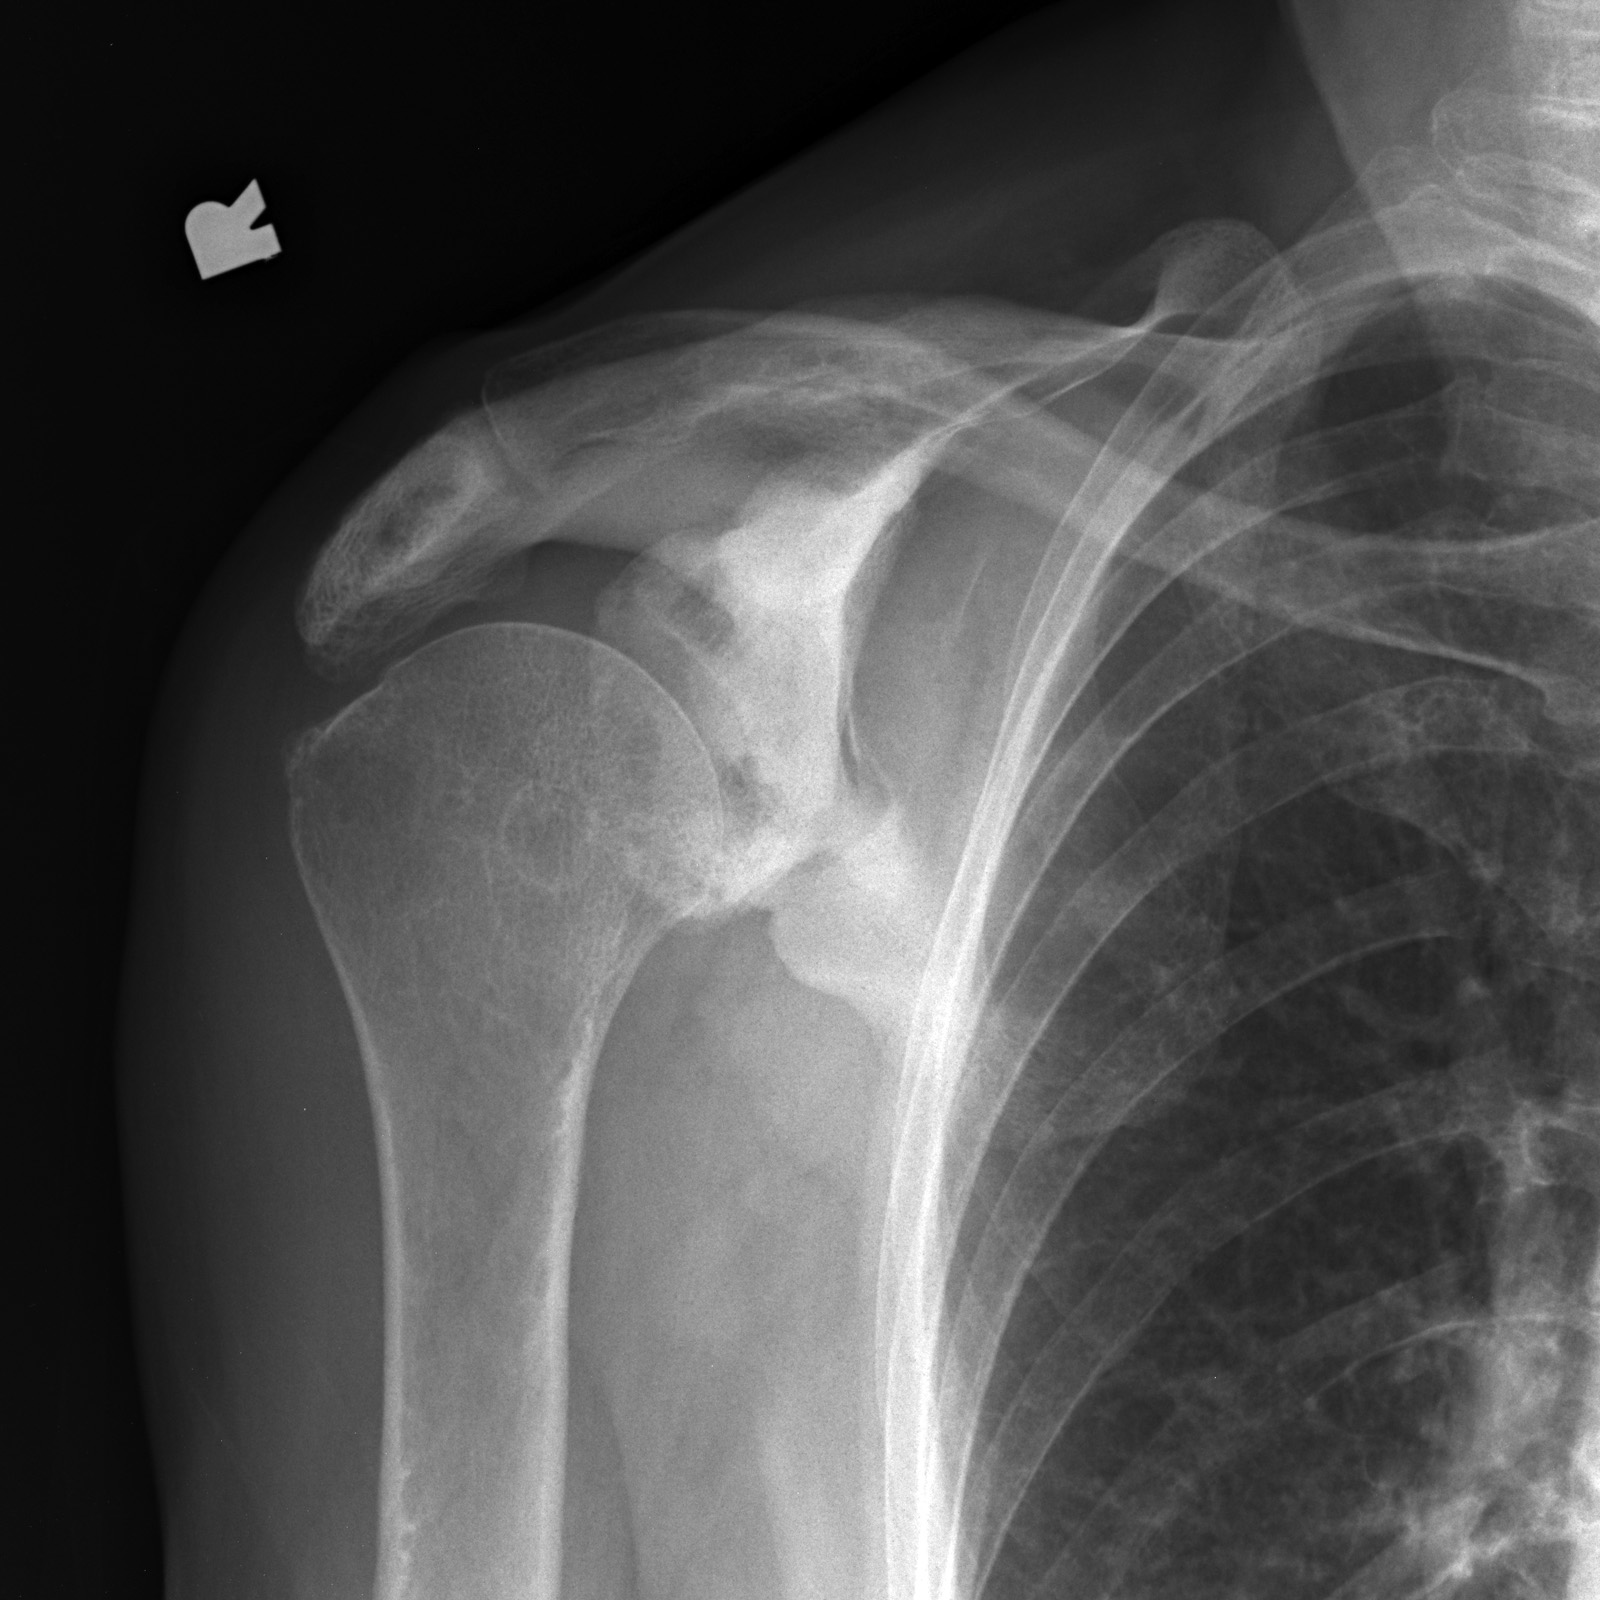

Рентгеновские снимки и визуализация болезни Педжета

Раздел: Мудрость в объективе